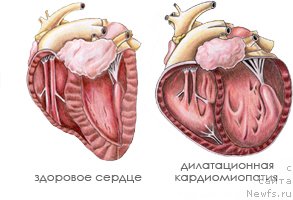

Классическая форма ДКМП характеризуется диффузным расширением всех камер сердца, нарушением сократительной функции миокарда, быстрым развитием сердечной недостаточности и нарушений ритма. При патологоанатомическом исследовании сердце сильно увеличено за счет расширения всех камер и имеет округлую форму (бычье сердце – cor bovinum). Определяют эксцентрическую гипертрофию миокарда, но при этом сердечная мышца кажется истонченной в результате выраженной дилатации полостей. Фиброзные кольца атриовентрикулярных клапанов растянуты, папиллярные мышцы истончены и ослаблены. При гистологическом исследовании выявляют дегенерацию, некроз кардиомиоцитов, множественные зоны фиброза и мононуклеарной инфильтрации.

Дилатационная кардиомиопатия (ДКМП) - заболевание сердечной мышцы, сопровождающееся нарушением насосной функции сердца с развитием застойной (хронической) сердечной недостаточности.

Причины дилатационной кардиомиопатии

Дилатация (от латинского dilatatio) - это расширение, растяжение камер сердца. При ДКМП происходит расширение преимущественно левого желудочка сердца, а по мере развития сердечной недостаточности и остальных камер. ДКМП - это истончение стенок желудочков по причине развития дистрофических процессов в мышечных волокнах, в результате чего происходит нарушение их сократительной функции и снижается систолическая функция.